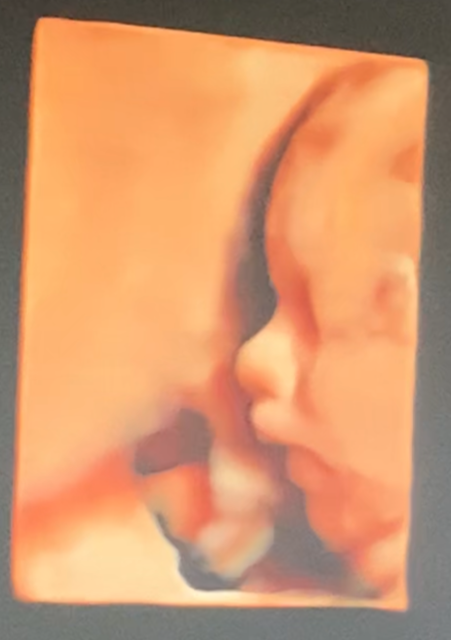

우리 부부는 입체 초음파를 찍으러 병원엘 다녀왔다.

쑥쑥이는 초음파를 갖다 대자마자

턱을 쓰으윽 들며 멋진 포즈로 엄마아빠한테 얼굴을 짠! 하고 보여줬다.

그 사이 쑥쑥이는 얼굴, 척추, 양손, 오른 발을 보여주었다.

그리고 기억에 남는 사진.

바로 얼굴 옆랑니 되시겠다.

누가 봐도 그녀를 닮은 눈/입/턱, 그리고 나를 닮은 코.

우리 쑥쑥이가 맞았다.

너무도 예뻤던 쑥쑥이.